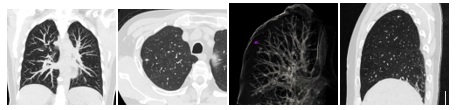

PEMERIKSAAN PARU BERDOSIS RENDAH

Kanker paru merupakan penyebab utama kematian akibat kanker di antara pria dan wanita di seluruh dunia. Sebagian besar kanker paru-paru ditemukan terlambat, sehingga tingkat kelangsungan hidup hanya selama5 tahun hanya 14%. Hanya 15% kanker paru-paru yang ditemukan pada stadium awal. Kelangsungan hidup lima tahun untuk kanker paru-paru yang dapat direseksi dini bisa mencapai 70% atau lebih tinggi. Skrining CT paru dapat mengarah pada deteksi dini dan oleh karena itu pengobatan dini dapat berhasil dilakukan.

Apakah itu pemeriksaan CT paru dosis rendah?

- Ini adalah pemeriksaan CT dosis rendah untuk mendeteksi kanker paru-paru pada pasien tanpa gejala apapun.

- Mampu memvisualisasikan berbagai kelainan paru-paru yang tidak dapat dilihat pada rontgen dada .

- Meningkatkan kemungkinan mendeteksi nodul paru-paru kecil, beberapa di antaranya mungkin bersifat kanker.